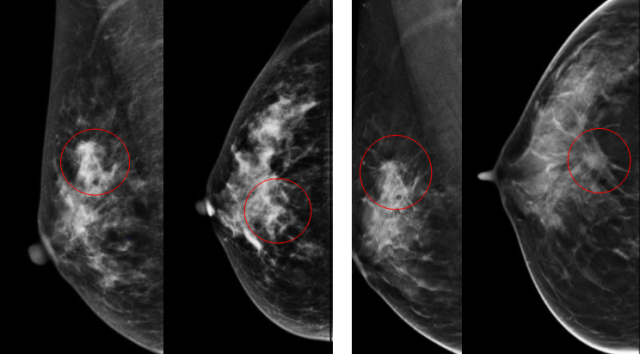

随着技术的发展,乳腺断层摄影技术(ASiR DBT)正在迅速取代传统数字乳腺X线摄影(FFDM)成为主要筛查方法,研究显示乳腺断层摄影技术(DBT)能比传统数字乳腺X线摄影(FFDM)多发现30%的癌症。亚洲女性乳腺腺体多为致密型,容易遮挡病灶而影响诊断,DBT扫描完成后,计算机利用算法把图像重建为平行于探测器且间距为1mm左右的影像,相对于传统的二维乳腺摄影技术,重建后的三维断层影像减少或消除了组织重叠和结构噪声的影响。

(左图)传统数字乳腺X线摄影(FFDM)

(右图)乳腺断层摄影技术(ASiR DBT)

右乳外上象限局限致密影

病理:右乳浸润性导管癌